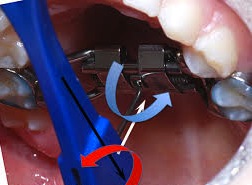

l’utilisation de l’appareil vous sera montré par l’orthodontiste ou le chirurgien.  L’activation sera débutée une semaine après l’intervention, jusqu’à ce que l’orthodontiste vous dise d’arrêter. En général, l’activation se fait matin et soir. Il est recommandé de noter sur une feuille les tours que vous avez réalisés.